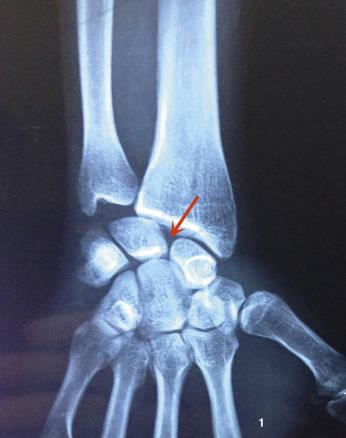

L’arthroscanner bien qu’invasif fournit une exploration fine et dépiste une éventuelle fracture ostéochondrale associée. Surtout, il montre l’importance de la déchirure ligamentaire.³ La fuite du liquide de contraste entre la médiocarpienne et la radiocarpienne signe le diagnostic (fig. 2).¹ ³